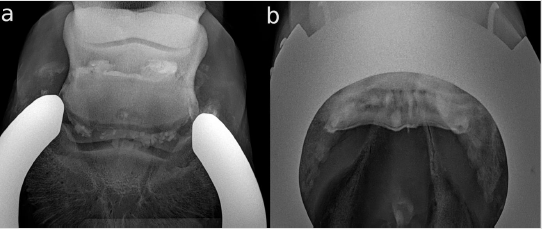

Horse 3 was presented at the hospital because of an acute onset of lameness in the right front two weeks previously. The referring vet made a DPr-PaDiO X-ray. There was a central radiolucent area in the navicular bone that was suspected of being an osseus cystlike lesion (OCLL). The lameness was alleviated by a distal digital nerve block in the clinic. The DPr-PaDiO was repeated and an additional PaPr-PaDiO X-Ray was done. The OCLL was seen again in both views. An intrabursal administration of corticosteroids was recommended and a systemic treatment with bisphosphonates as therapy. The DPr-PaDiO CE radiographs showed a radiopaque area exactly in the middle of the suspected OCLL. The proximal and distal border of the NB also seemed to be very irregular (Figure 2a). The finding could be revealed in the PaPr-PaDiO CE (Figure 2b). The diagnosis was a full thickness flexor cortex lesion including the subchondral bone and bursitis of the NB. The prognosis given was poor. The horse was three month better with the therapy. It was euthanized after three months because of the poor prognosis and the recurrent lameness.

Figure 2: Contrast-enhanced (CE) X-rays of horse 3; lateral is to the left.

a. Dorsoproximal-palmarodistal oblique (DPr-PaDiO) CE view; in the middle of the suspected osseus cyst-like lesion (OCLL)

is a round-shaped radiopaque shadow arising from an accumulation of CM at the level of the navicular bone. The proximal

border of the NB is very irregular, which is suspected of being a massive adhesion between the collateral sesamoidean ligament

(CSL) and the DDFT. There also seems to be an adhesion on the lateral sight of the distal border.

b. DPr-PaDiO CE: the suspected focal pool of CM is in the middle of the navicular bone and, thus, proof of the suspected OCLL.

There is an irregularity in the border of the CM medial to the ridge of the navicular bone. This finding is indicative of a lesion

in the DDFT.